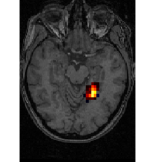

face

vs house

TV-l1

Graph-net

Social sparsity

Finally, an important aspect of the brain decoders is whether they segment well the brain regions that support the decoding. Such a question is hard to validate, yet there is evidence that TV- is a good approach [5]. Fig. 2 displays the decoder maps for the object-recognition tasks. For these tasks, we expect prediction to be driven by the functional areas of the visual cortex [27]. Indeed, the maps outline regions in known visual areas. The graph-net maps are much more scattered and less structured than the others. Conversely, the social sparsity maps are sparser and outline a smaller number of clusters.